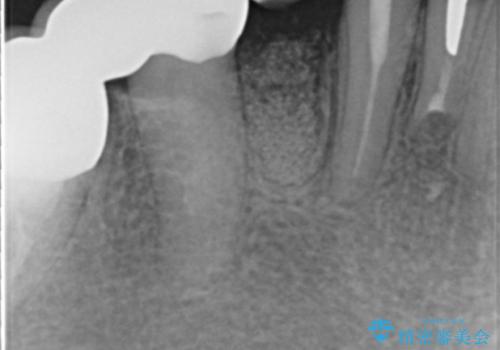

X線写真および歯周組織検査より、歯の破折 周囲骨の高度な吸収が認められました。

抜歯後、インプラントによる審美・機能改善を希望されたのでインプラント埋入に先立ち吸収した骨の再生を計画します。

歯を失う原因が虫歯や根尖病変などはなく、歯周病や歯の破折等周囲の骨を吸収する原因の場合はインプラント治療を行うに先立ち骨の造成が必要なことがあります。